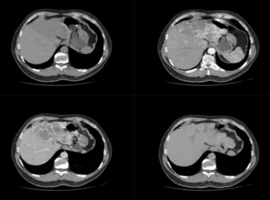

Diffuse Hepatic Hemangiomatosis with Left-Lobe Predominance

Volume 8, Issue 1

:

Read More